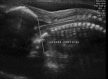

The advance in the imaging tools during the pregnancy (ultrasound and magnetic resonance) allowed the early diagnose of many fetal diseases, including the neurological conditions. This progress brought the neurosurgeons the possibility to propose treatments even before birth. Myelomeningocele is the most recognized disease that can be treated during pregnancy with a high rate of success. Additionally, this field can be extended to other conditions such as hydrocephalus and encephaloceles. However, each one of these diseases has nuances in the diagnostic evaluation that should fit the requirements to perform the fetal procedure and overbalance the benefits to the patients. In this article, the authors aim to review the neurosurgical aspects of the antenatal management of neurosurgical conditions based on the experience of a pediatric neurosurgery center.